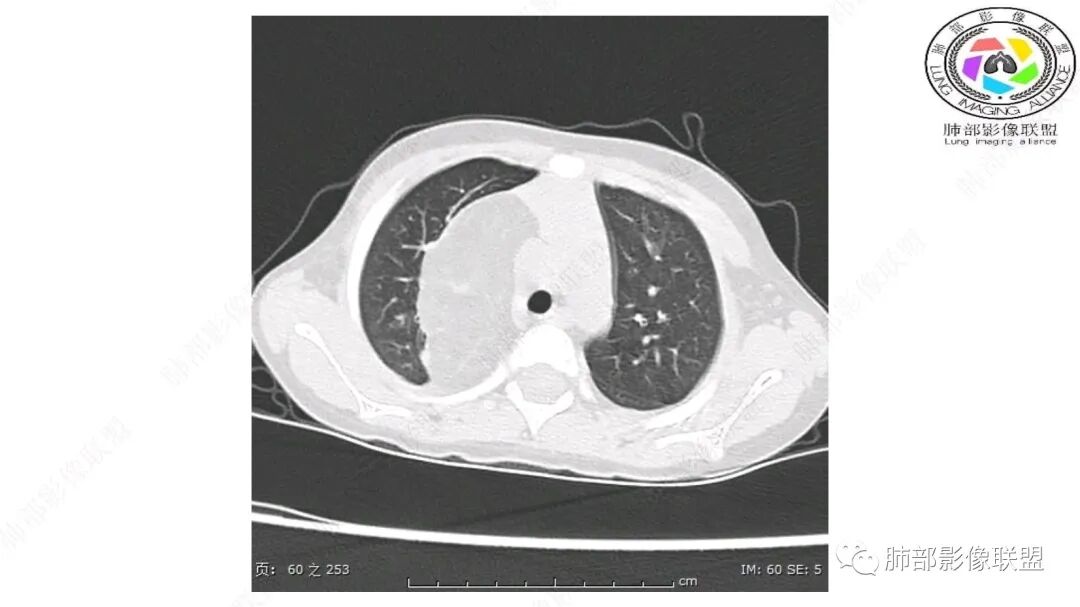

第一个问题:定位:肺内?纵隔?

病灶属于交界区,主体位于肺内,占位效应明显,前方突入胸壁,胸腺受压变形,胸膜显示欠清楚;病灶包绕上叶肺动脉;似乎有体动脉供血。符合肺内的点:包绕上叶肺动脉分支;符合纵隔的点:前方似乎突入胸壁,与胸腺关系比较密切,但是与上腔静脉的关系提示病灶不支持纵隔来源,前纵隔的常规会将上腔静脉受压后移、外移,这是不符合的。

从这个角度符合肺内的,有一点不太踏实的是:似乎突入前胸壁。

2.肺动脉穿行也许是肺内来源最重要支持点!